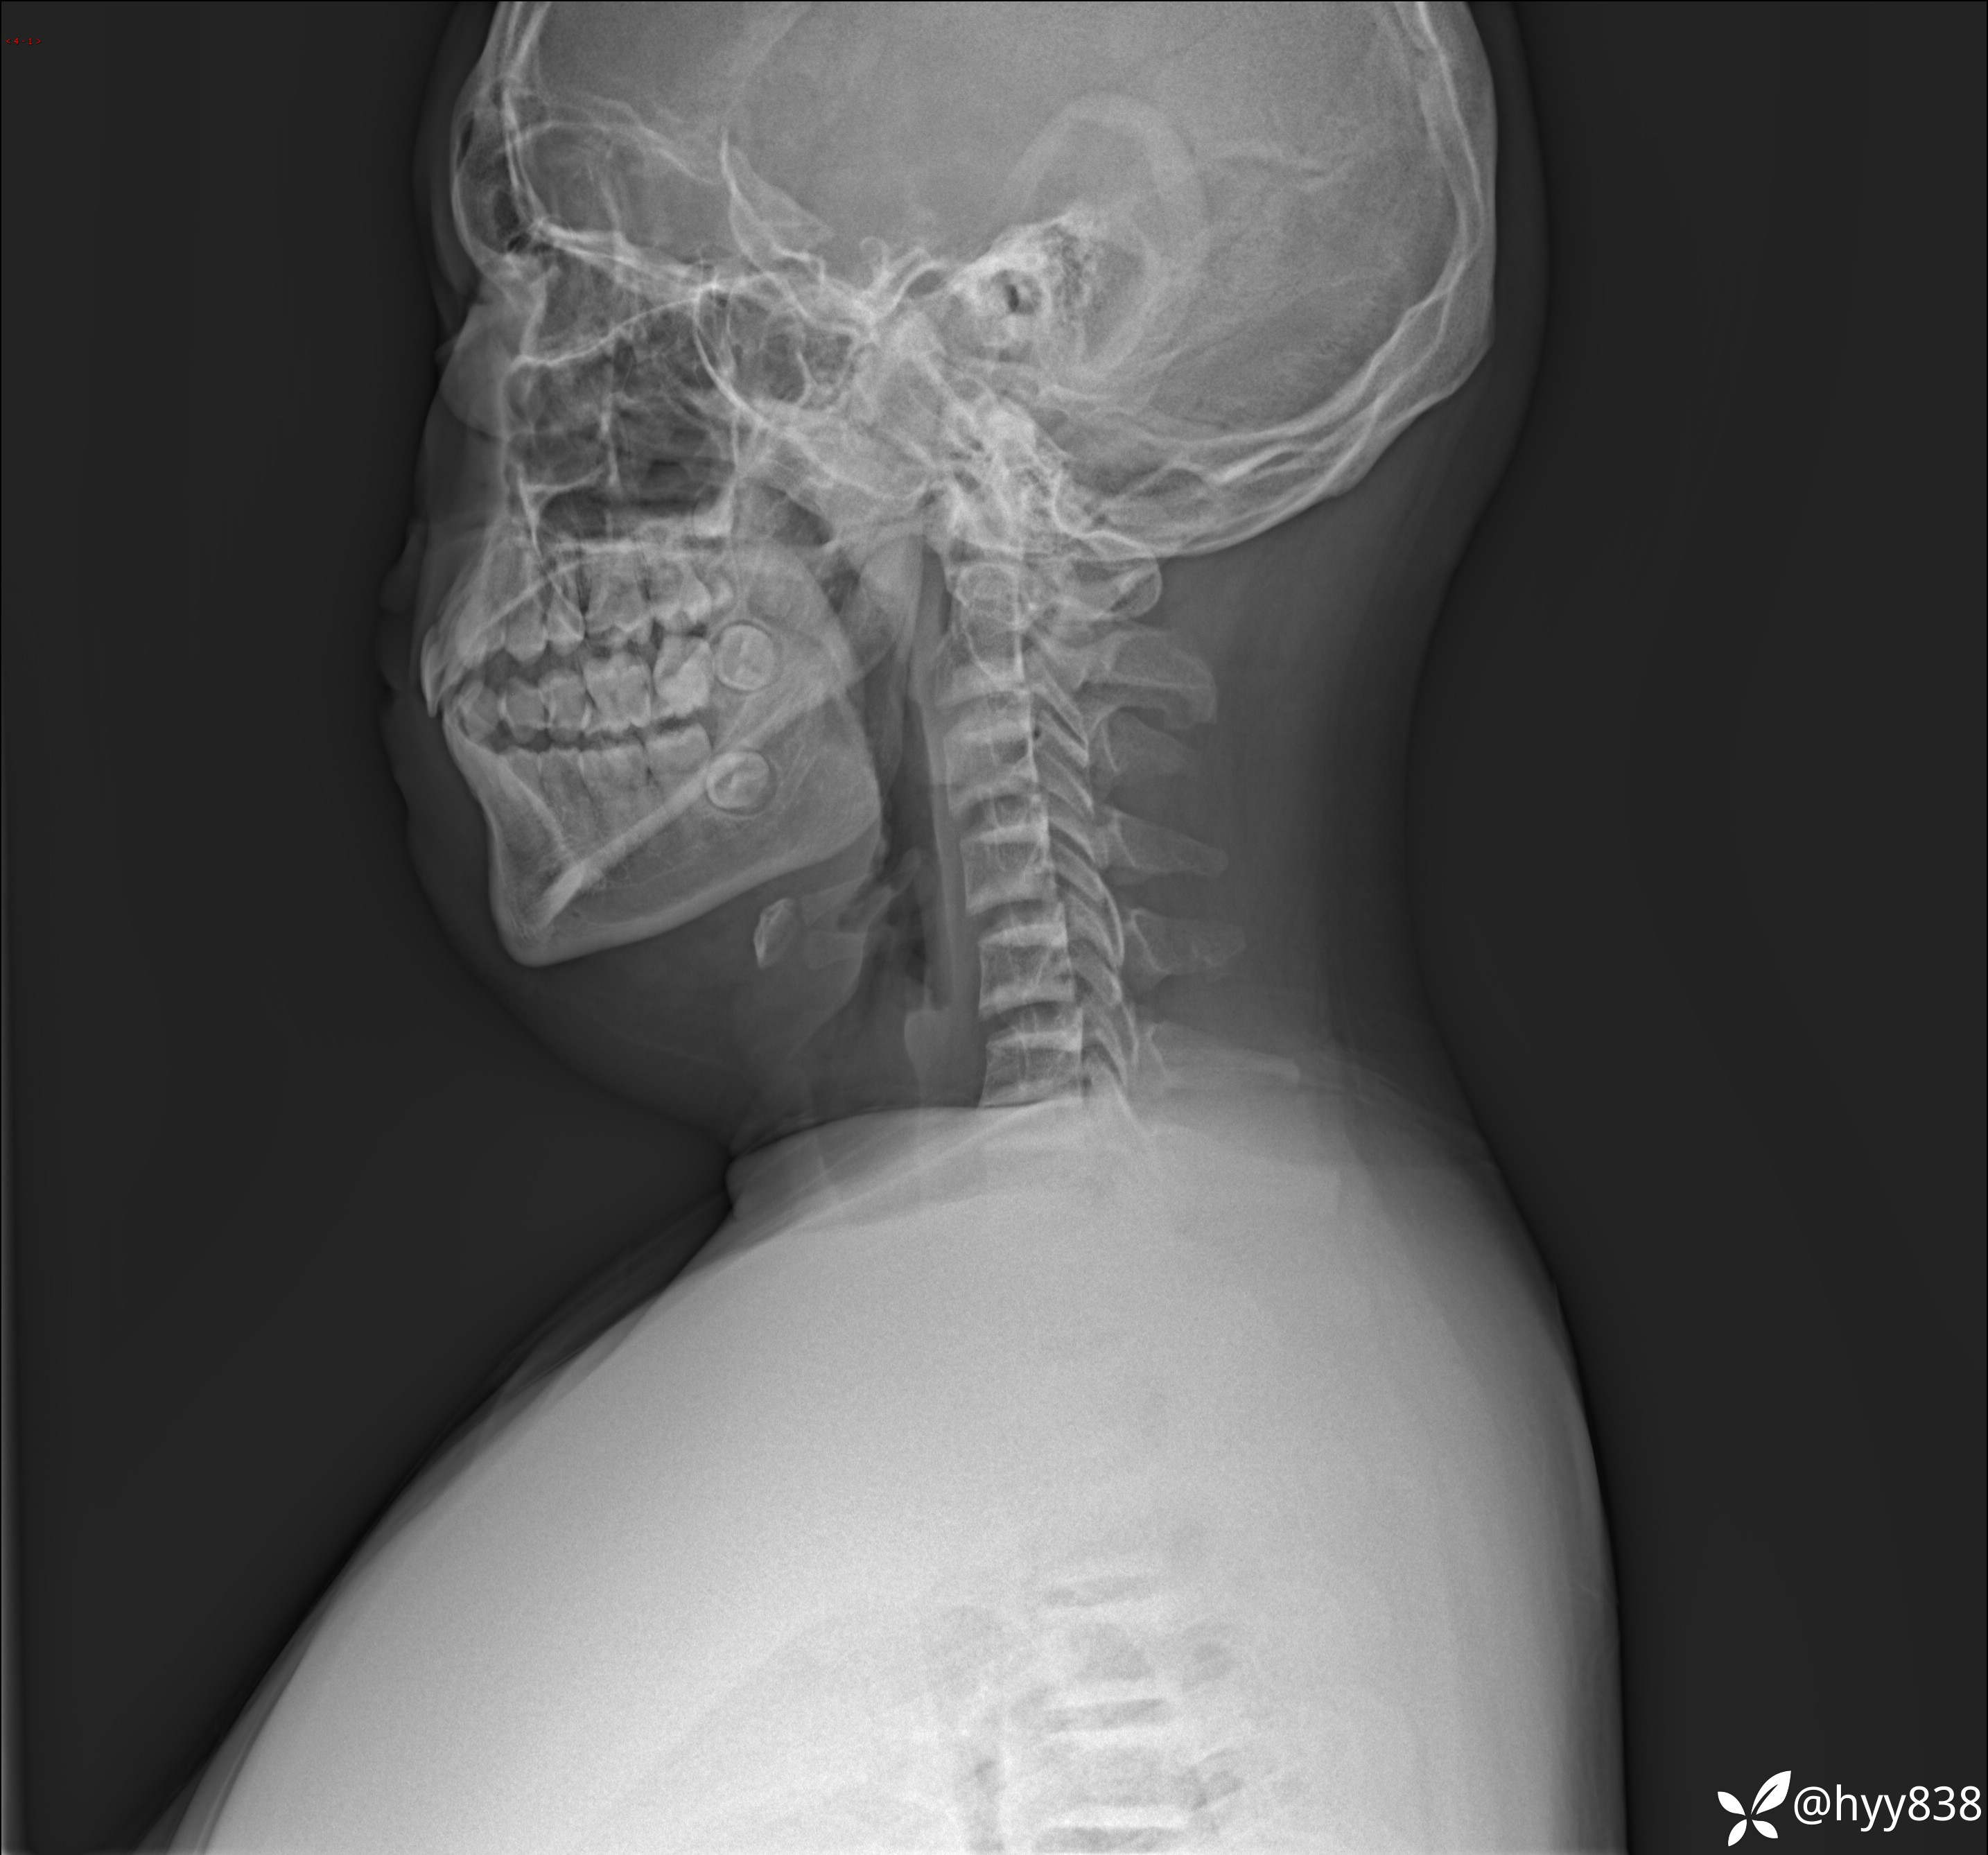

性别:男

年龄:13岁

简要病史:脊柱侧弯复诊

颈椎、胸椎、腰椎正侧位片